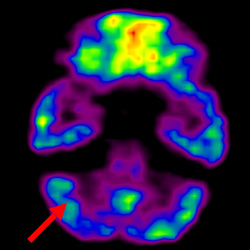

細(xì)胞治療前 PET CT 掃描顯示神經(jīng)組織中的藍(lán)/黑色區(qū)域,表明腦癱引起的大腦損傷。